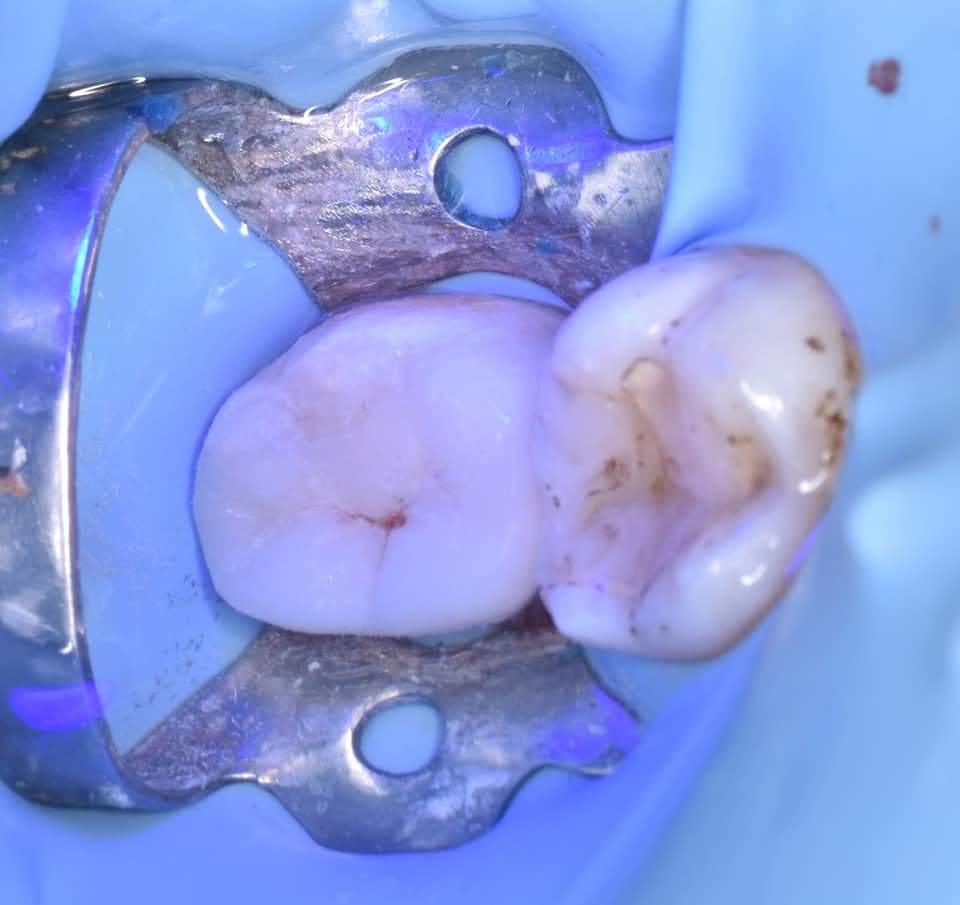

Immediate result

When you dont have the glycerin in that time , just immerse the tooth with water and cure through it for Oxygen inhibition layer removal

Immediate result direct view